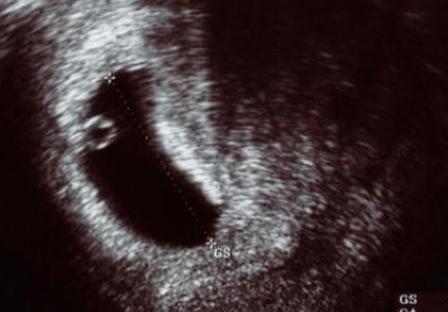

Во время менструального цикла ваше тело проходит через процесс, который подготавливает матку к заботе об оплодотворенной яйцеклетке и делает ее питательной средой для плода. Если оплодотворенная яйцеклетка не попадает в матку, у вас начинается менструальный период, и слизистая оболочка матки, над созданием которой так усердно работало ваше тело, отторгается. Однако, когда происходит оплодотворение, бластоциста поселяется в слизистой оболочке матки, состоящей из крови и ткани, зарываясь в слизистую оболочку до тех пор, пока она не будет надежно прикреплена. Это может вызвать некоторый дискомфорт и спазмы в животе . Во время имплантации яйцеклетки часть слизистой оболочки может отделиться, чтобы освободить место. В этом нет ничего страшного и это совершенно нормально. Кровь или ткань, которые отпадают от слизистой оболочки матки, затем выходят наружу в виде имплантационного кровотечения.